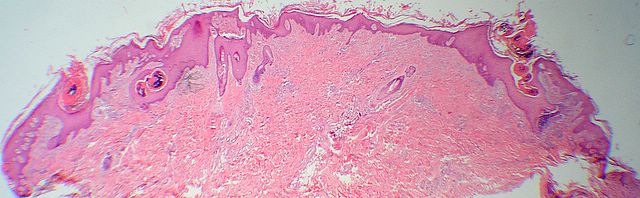

Descripcion histologica

Diagnostico